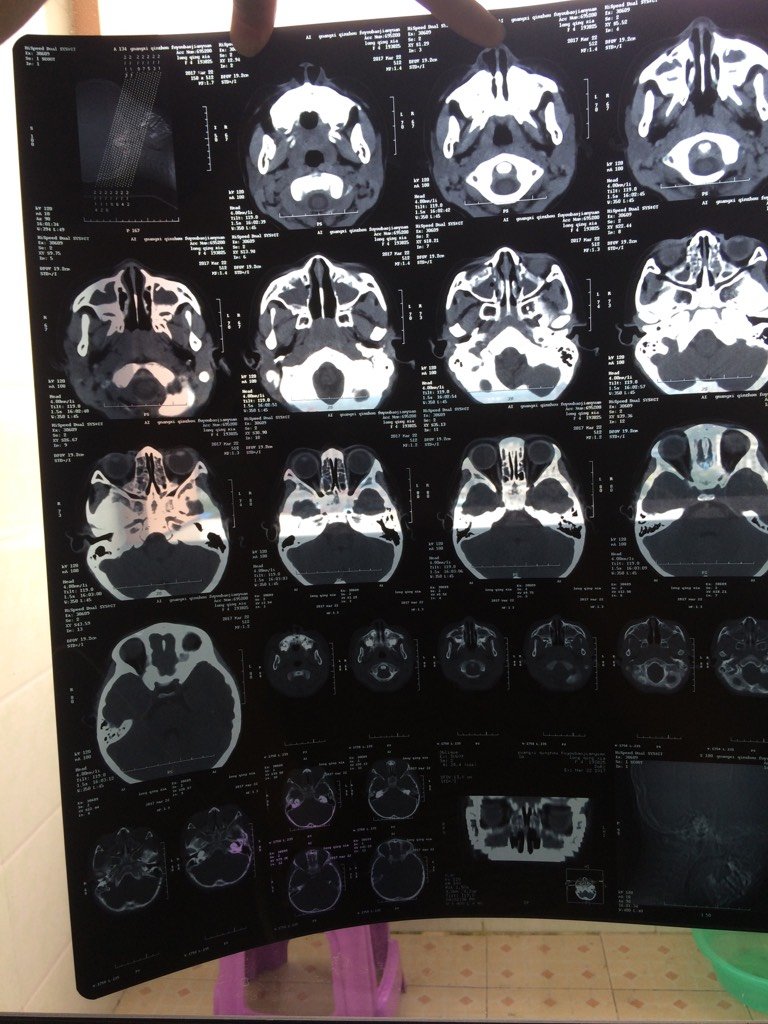

宝宝50天眼珠子老是往下看,医生说是落日征,说是大脑有问题,这是昨天做的CT,宝宝有脑积水吗,会影 宝宝50天眼珠子老是往下看,医生说是落日征,说是大脑有问题,这是昨天做的CT,宝宝有脑积水吗,会影响以后吗 点击展开 旧梦难温 // 2017-03-25 13:43 为您推荐: 其他回答 咨询医生吧 。航航妈妈。 2017-03-27 16:25 咨询下医生…… 520幸福宝贝1314 2017-03-27 13:08 咨询医生,,, 麻麻爱丞丞 2017-03-26 10:45 问问医生, 永远牵挂你的人是我 2017-03-26 07:50 看医生??? 风语者_BfEd 2017-03-25 23:00 加载更多 相关问题 我家宝宝现在五个月了,发现是脑积水,有明显落日症状,头变大 在哈尔滨医科大学附属第二医院做的CT 宝宝四个月的时候肺炎做过一次ct,现在八个月太阳穴处有血管瘤,去医院治疗医生说还要做头部ct,这些 怀孕五个多月了,昨天做彩超检查,医生说宝宝一侧肾脏有积水,现在又不能吃药,我很担心,不知道有没有其